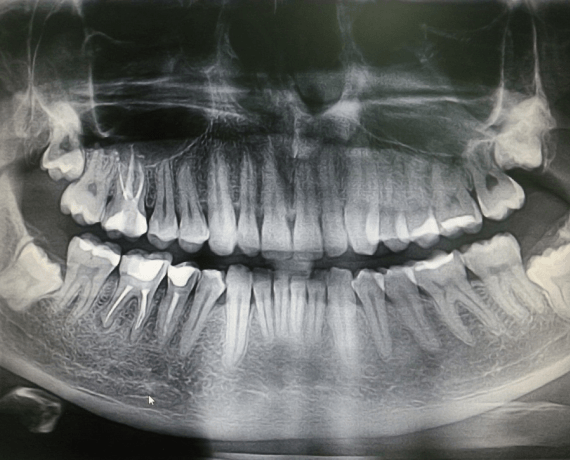

Примеры ортопантомограмм и их анатомия

Раздел: Фотоэссе